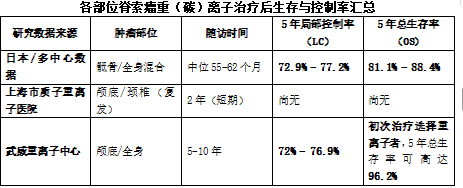

从现有临床数据来看,重(碳)离子治疗为脊索瘤提供了一种高效、低毒的治疗选择,尤其适合手术难以切除或术后复发的患者。以下是基于循证数据的量化分析:

3.1 疗效数据:局部控制率与生存率

重(碳)离子治疗的突出优势在于很高的局部控制率(LC),一年的局控率可以达到100%,重(碳)离子治疗脊索瘤的有效率近100%。由于脊索瘤对常规放疗不敏感,且毗邻重要器官,重离子凭借其物理和生物学双重优势,能给予肿瘤根治性剂量。对于5cm以下的小的脊索瘤和部位较低,不容易发生神经损伤的病例,手术也是很好的选择,一旦脊索瘤的体积大,手术出现二便失禁和下肢运动功能丧失的可能性大的,就一定要选择重离子。重离子对小的脊索瘤根治性效果当然好,对于体积巨大的,比如10-20cm及以上的脊索瘤,就能体现重离子独特的优势,是不可替代的选择。

关键解读:

· 初治 vs. 复发:数据显示,如果是初次治疗且未接受过放疗,5年总生存率可高达96.2%;而一旦手术了,而术后复发了,那么疗效显著下降。如果是术后复发或二次放疗,生存率会显著下降至约50%。这提示抓住首次治疗机会至关重要。

· 长期控制:对于颅底脊索瘤,10年局部控制率仍可维持在54%左右,显示出治疗的长期有效性。